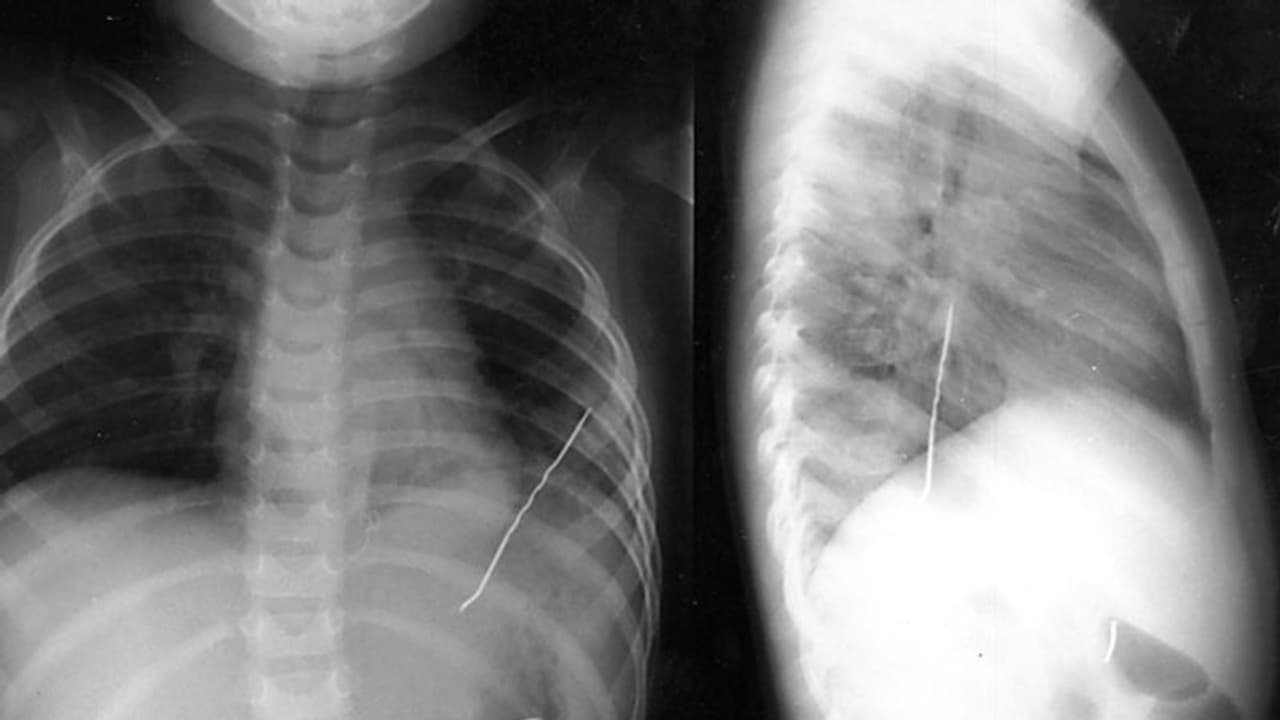

ശിരോവസ്ത്രത്തിൽ കുത്താൻ വേണ്ടി പല്ലിനിടയിൽ കടിച്ചു പിടിച്ച പിൻ അറിയാതെ വിഴുങ്ങുകയായിരുന്നു. ഉടൻ തന്നെ വീട്ടുകാർ പെൺകുട്ടിയെ തൊട്ടടുത്തുളള ആശുപത്രിയിൽ എത്തിച്ചു. തുടർന്ന് എക്സ് റേ എടുക്കുകയും പിൻ ശ്വാസകോശത്തിൽ കുടുങ്ങിയ നിലയിൽ കണ്ടെത്തുകയുമായിരുന്നു. എൻഡോസ്കോപ്പി വഴി പിൻ പുറത്തെടുക്കാൻ ഡോക്ടർമാർ ശ്രമിച്ചെങ്കിലും നടന്നില്ല.

തുടർന്ന് ഗോവയിലെ മൂന്ന് മെഡിക്കൽ കോളേജുകളിലും രണ്ട് സ്വകാര്യ ആശുപത്രികളിലും ചികിത്സയ്ക്കായി പോയിരുന്നെങ്കിലും ഡോക്ടർമാർക്കൊന്നും പെൺകുട്ടിയെ സഹായിക്കാൻ കഴിഞ്ഞില്ല. ശസ്ത്രക്രിയയിലൂടെ പിൻ പുറത്തെടുക്കാമെന്ന് ഡോക്ടർമാർ നിർദ്ദേശിച്ചിരുന്നെങ്കിലും പെൺകുട്ടിയുടെ മാതാപിതാക്കൾ സമ്മതിച്ചില്ല. പിന്നീട് ചെമ്പൂരിലെ സെൻ മൾട്ടിസ്പെഷ്യലിറ്റി ആശുപത്രിയിലെത്തി ബ്രോങ്കോസ്കോപ്പി വഴി പിന് പെൺകുട്ടിയുടെ ശ്വാസകോശത്തിൽനിന്ന് പുറത്തെടുക്കുകയായിരുന്നു.